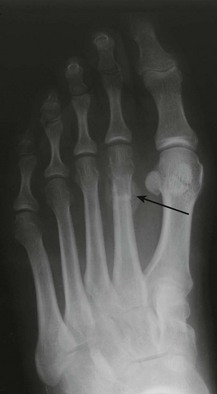

Forefoot pain, often localised to the second metatarsal, after excessive activity such as trekking, marching or dancing, suggests a stress fracture (Fig. 14.53). Symptoms are relieved by rest and aggravated by weight bearing. X-rays in the first week may be normal.